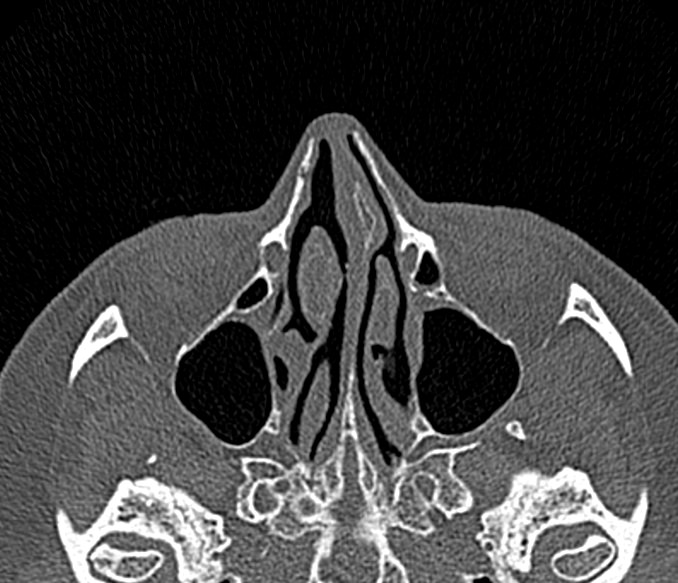

Золотым стандартом в диагностике патологических процессов пазух носа является мультиспиральная компьютерная томография, которая является быстрым безболезненным и неинвазивным (то есть без вмешательства в организм) способом исследования состояния синусов. Метод основан на проникающей способности ионизирующего излучения и получения изображений органов и тканей организма за счет разной степени поглощения ими рентгеновских лучей.

На основе полученных данных цифровые приложения томографов создают трехмерные реконструкции пазух носа, что позволяет оценить пространственное взаимоотношение анатомических структур и помогает в диагностике патологии околоносовых пазух.

Мультиспиральная компьютерная томография дает информацию о состоянии полости носа, носовой перегородки, степени воздушности околоносовых пазух, путей дренирования синусов, состоянии слезных каналов. Сканирование позволяет оценить толщину слизистой, наличие патологического содержимого в просвете пазух (уровня «жидкости»), выявить опухолевые образования. С помощью КТ можно провести точную диагностику травматических повреждений костей лицевого черепа, определить локализацию инородных тел, попавших в полости синусов.

С помощью объемной реконструкции можно перед оперативным вмешательством увидеть особенности анатомии ЛОР-органов, определить точное расположение патологического очага по отношению к окружающим тканям. Компьютерная томография помогает в диагностике аномалий развития придаточных пазух носа, слезоотводящих каналов.